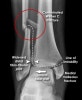

AP, lateral, Mortise view를 보면 대부분의 골절이 진단됩니다.

돌림손상 시에는 거골 바깥쪽 관절면의 골연골성 골절이 일어날 수 있습니다. Mortise view에서 가장 잘 나타나며 복합골절 평가 시에는 CT가 필요할 수 있습니다.

X-ray : 내과 골절(Medial malleolar fracture)